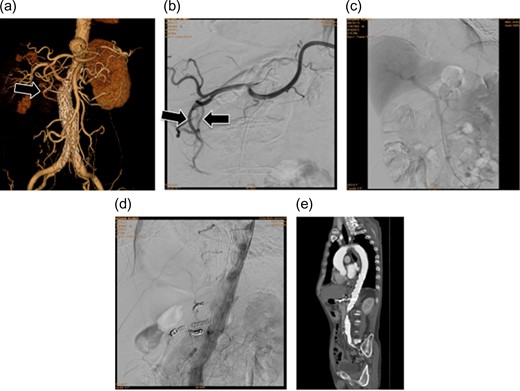

The SMA was cannulated and selectively imaged. Communication between the SMA and peripheral celiac artery was observed via the gastroduodenal artery. Selective coil embolization was performed in the common hepatic, splenic and right gastric arteries. The coils were placed centrally to preserve the gastroduodenal and proper hepatic arteries.

(a) Preoperative three-dimensional computed tomography (3D-CT) angiography showing the aneurysm. An arcade for the celiac and superior mesenteric arteries was confirmed via the gastroduodenal artery (arrow). (b) Intraoperative image of the celiac artery. As on the 3D-CT images, an arcade via the gastroduodenal artery was confirmed (arrow). (c) Portal phase image of the SMA. The liver is imaged during blood flow from the portal vein, confirming that the liver will be supplied with blood even if the hepatic artery blood flow decreases. (d) Angiography after placing the stent graft. No endoleaks, including Type II endoleaks from the celiac artery, are observed. Accordingly, the treatment was deemed effective. (e) Postoperative contrast-enhanced CT. No endoleaks are observed, so the treatment was considered successful.